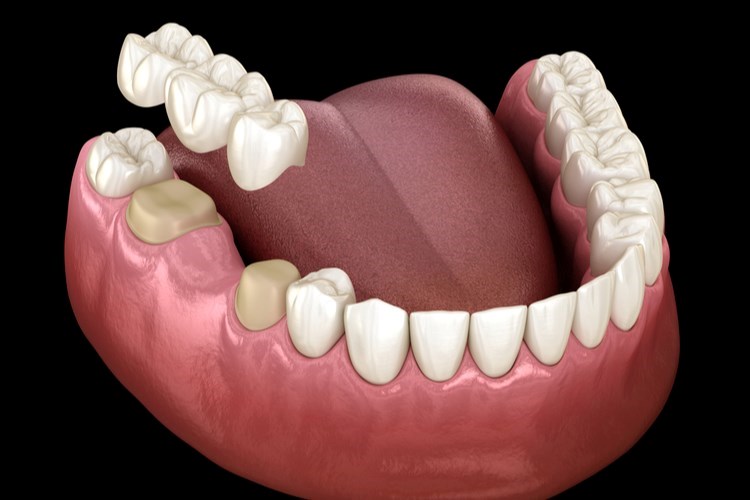

כאשר יש צורך בפתרון שיקומי למצבים שונים של שיניים שבורות, שיניים שעברו טיפול שורש, שיניים שעברו שחיקה או עששת נרחבת, או במקרים של חוסר שיניים לאחר עקירה, הפתרון המוצלח ביותר הוא כתר המתלבש על השן.

שני סוגי הכתרים מיועדים לאותה מטרה אך עדיין יש מספר הבדלים ביניהם:

"כתר חרסינה עשוי מליבת מתכת אשר מאוחה אליו בחרסינה. לעומת זאת כתר מזירקוניה עשוי מזירקונים אוקסיד, ואינו כולל מתכת. משום שזירקוניה עשוי מחומר לבן, אין בו אותה ליבה אפורה שאנו רגילים לראות בכתר חרסינה.

"כמו כן, בכתר זירקוניה אפשר להגיע לרמות יותר גבוהות של אסתטיקה. זו הסיבה שבכתרים מזירקוניה אנו משתמשים בעיקר בשיניים קדמיות, הכתרים הללו לא משפיעים ולא משנים את גוון השיניים שעליה הם מתלבשים.

"כתר חרסינה, לעומת זאת, יכול לשנות את צבע השן בשל המתכת שיש בו. כששמים כתר מחרסינה, על רופא השיניים מוטל לשייף חלק גדול מהשן כדי למנוע השתקפות של המתכת מבעד לחרסינה. התוצאה היא שהשן יותר שברירית ועלול להיווצר בה שינוי גוון".